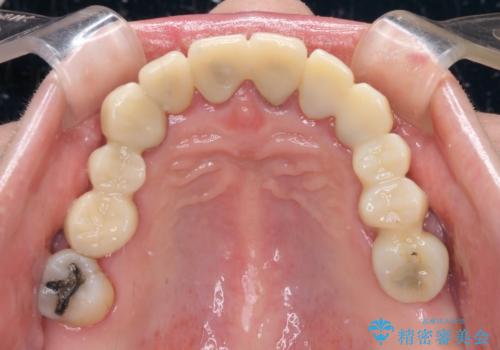

- 歯茎からの出血、入れ歯、歯の欠損、デコボコの前歯などを気にして来院された患者様です。

大の歯科治療嫌いとのことでしたが、今回の治療を契機にしっかりと治療を行いたいとのことでした。

まずは抜歯が必要な歯を抜歯した上で仮歯に置き換え、インプラント埋入や歯周外科処置、根管治療を行うこととしました。

歯肉の状態が落ち着いた後に下顎の矯正治療を行い、その後補綴治療を行うこととしました。